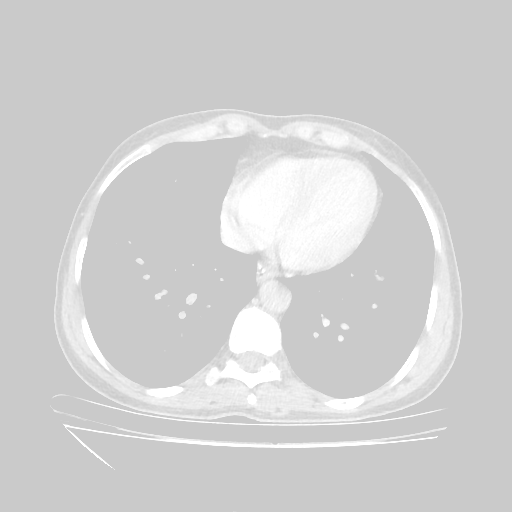

Slice 70 Targeting Evaluation

Slice: Slice_70

Conversion: NATIVE β†’ VENOUS

Reconstructed NATIVE CT scan (cycle consistency)

No window - Raw intensity values